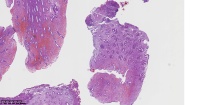

请老师们帮看看这些子宫内膜

性别

女

年龄

47岁

临床诊断

一般病史

子宫内膜息肉

标本名称

大体所见

图2

增殖性子宫内膜,子宫内膜息肉